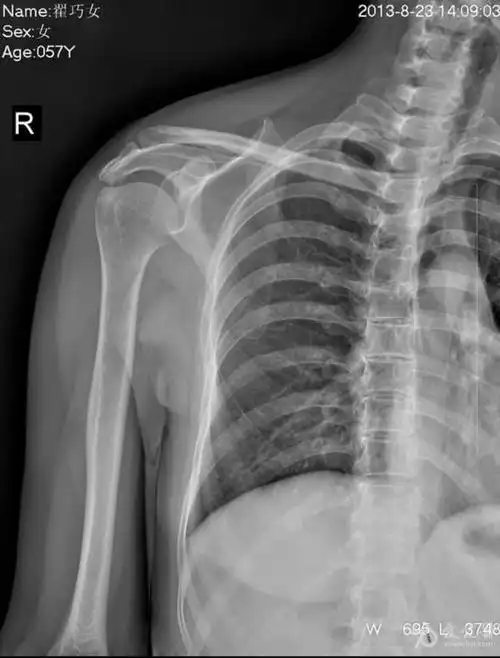

x片示右肩关节冈上肌附着点见多发结节状高密度影,ct扫描示钙化灶,ct